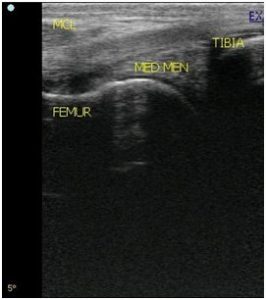

- Diagnostic imaging- radiography or ultrasound

- Radiography, ultrasound

A high quality ultrasound is a very valuable imaging tool for evaluating and diagnosing a wide range of conditions primarily but not limited to soft tissue. Musculoskeletal structures such as tendons, ligaments, joints, muscles and bone surfaces may be evaluated for signs of injury or infection. Once an injury is found, ultrasound allows for monitoring healing progress. It can be used for ultrasound guided injections of structures such as the sacroiliac and cervical joints. Ultrasound can aid in diagnosing the cause of colic and other abdominal conditions as well as conditions of the thorax such as pleuropneumonia and lung abscesses. Another very common use of ultrasonography is to monitor reproductive cycles and pregnancy in the broodmare.